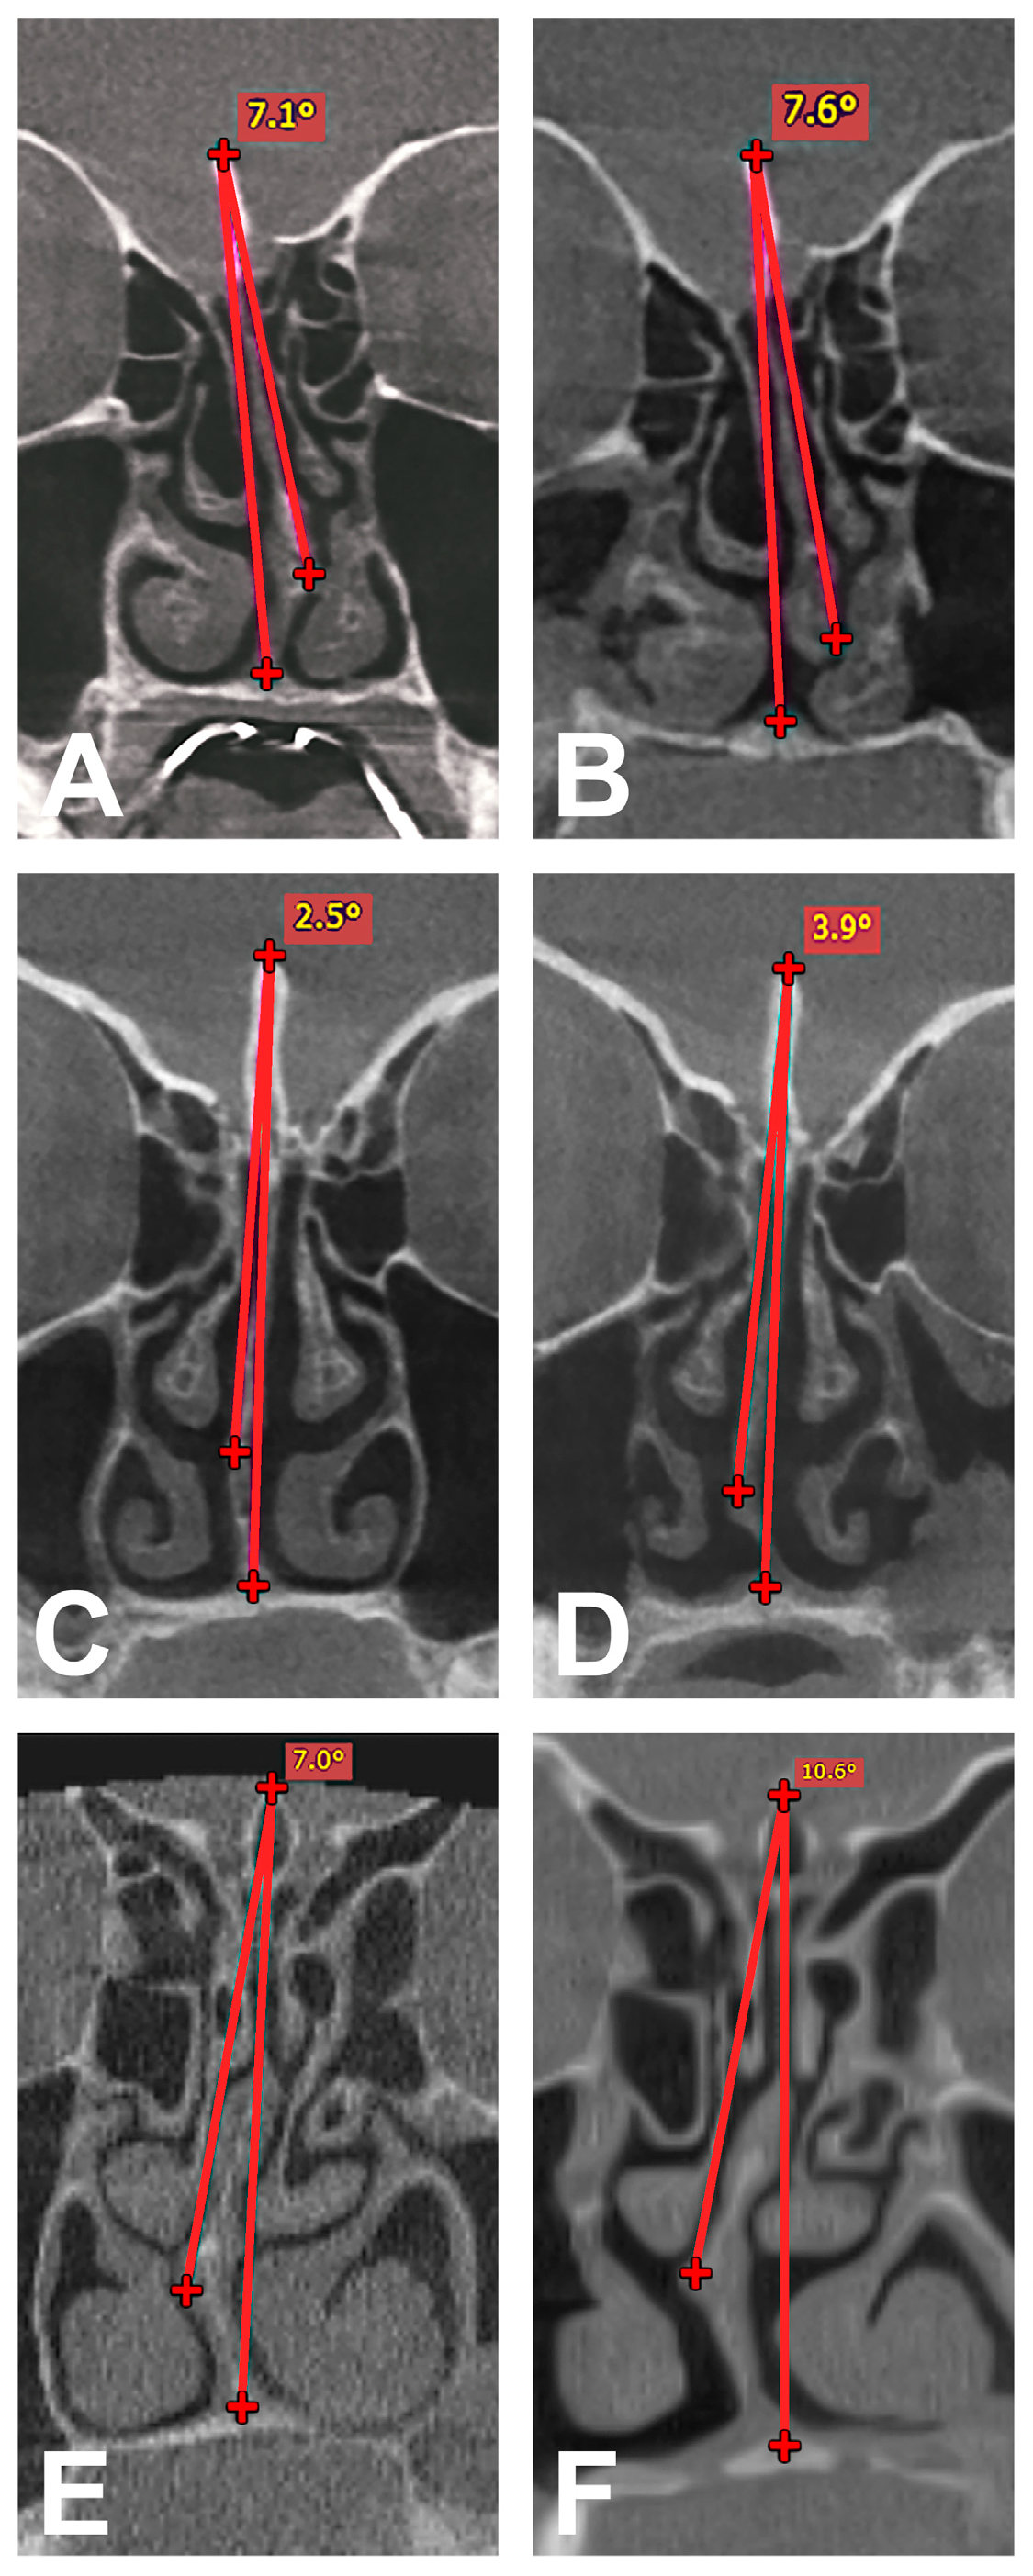

2.3. Radiological Analysis

2.5. Determination of NSD